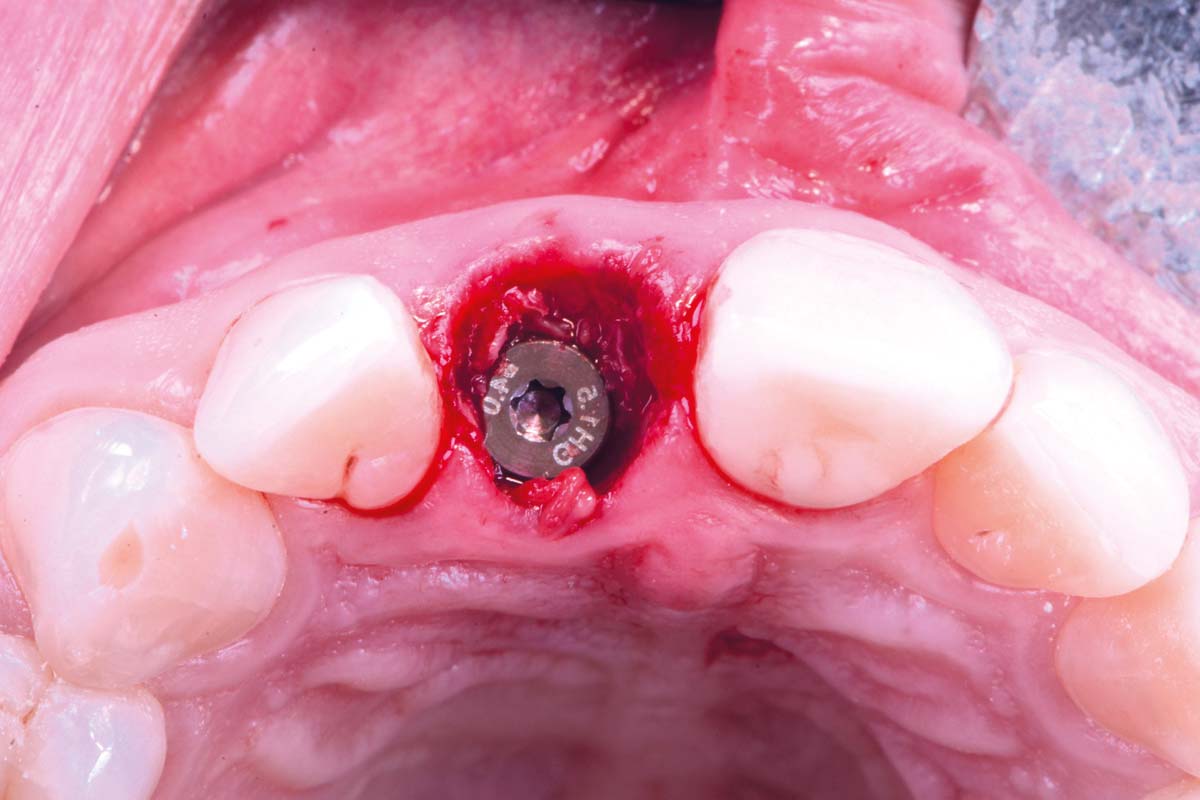

Initial clinical situation - Central incisors with dental destruction and periapical pathology